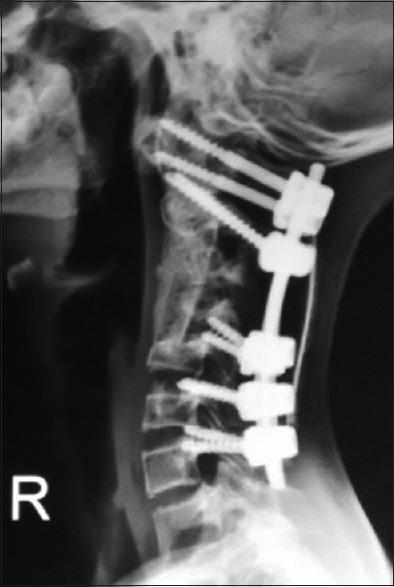

A 14-year-old boy presented with gradually worsening spastic quadriparesis and cervical kyphotic deformity as a consequence of laminectomy for tumor debulking and chemoradiotherapy done 2 years prior for cervical primitive neuroectodermal tumor. Problems to be addressed particularly to the case were a rigid kyphosis of 102.7°, poor soft-tissue coverage, internal gibbus compressing cord, perched facets, and superficial location of cord. The surgery was staged, in that the first anterior release was done with gradually increasing traction to correct the kyphosis progressively. Posterior instrumentation was done in the second stage. Finally, anterior reconstruction with tricortical iliac bone grafting was done. The patient regained full power with complete union at the end of 18 months. Irradiation of tumor along with laminectomy results in loss of posterior tension band which results in progressive kyphotic deformity in children. A staged plan of surgical interventions can help in postoperative correction of deformity with circumferential union and prevention of recurrence. This article describes successful treatment of a patient with postlaminectomy cervical kyphosis with 77° of correction achieved postoperatively and also highlights the importance of anterior and posterior reconstructions to achieve a stable vertebral column.

一名14岁男孩因两年前为治疗颈椎原始神经外胚层肿瘤而进行的肿瘤减瘤椎板切除术和放化疗,出现逐渐加重的痉挛性四肢瘫和颈椎后凸畸形。该病例需要特别解决的问题包括102.7°的僵硬后凸、软组织覆盖差、内部驼背压迫脊髓、关节突高位以及脊髓位置表浅。手术分阶段进行,首先进行前路松解,逐渐增加牵引以逐步矫正后凸。第二阶段进行后路内固定。最后,进行三皮质髂骨移植的前路重建。患者在18个月结束时恢复了全部肌力,实现了完全愈合。肿瘤放疗联合椎板切除术会导致后张力带丧失,从而导致儿童出现进行性后凸畸形。分阶段的手术干预计划有助于术后通过环形愈合矫正畸形并预防复发。本文描述了一名椎板切除术后颈椎后凸患者的成功治疗,术后实现了77°的矫正,同时强调了前后路重建对于实现稳定脊柱的重要性。